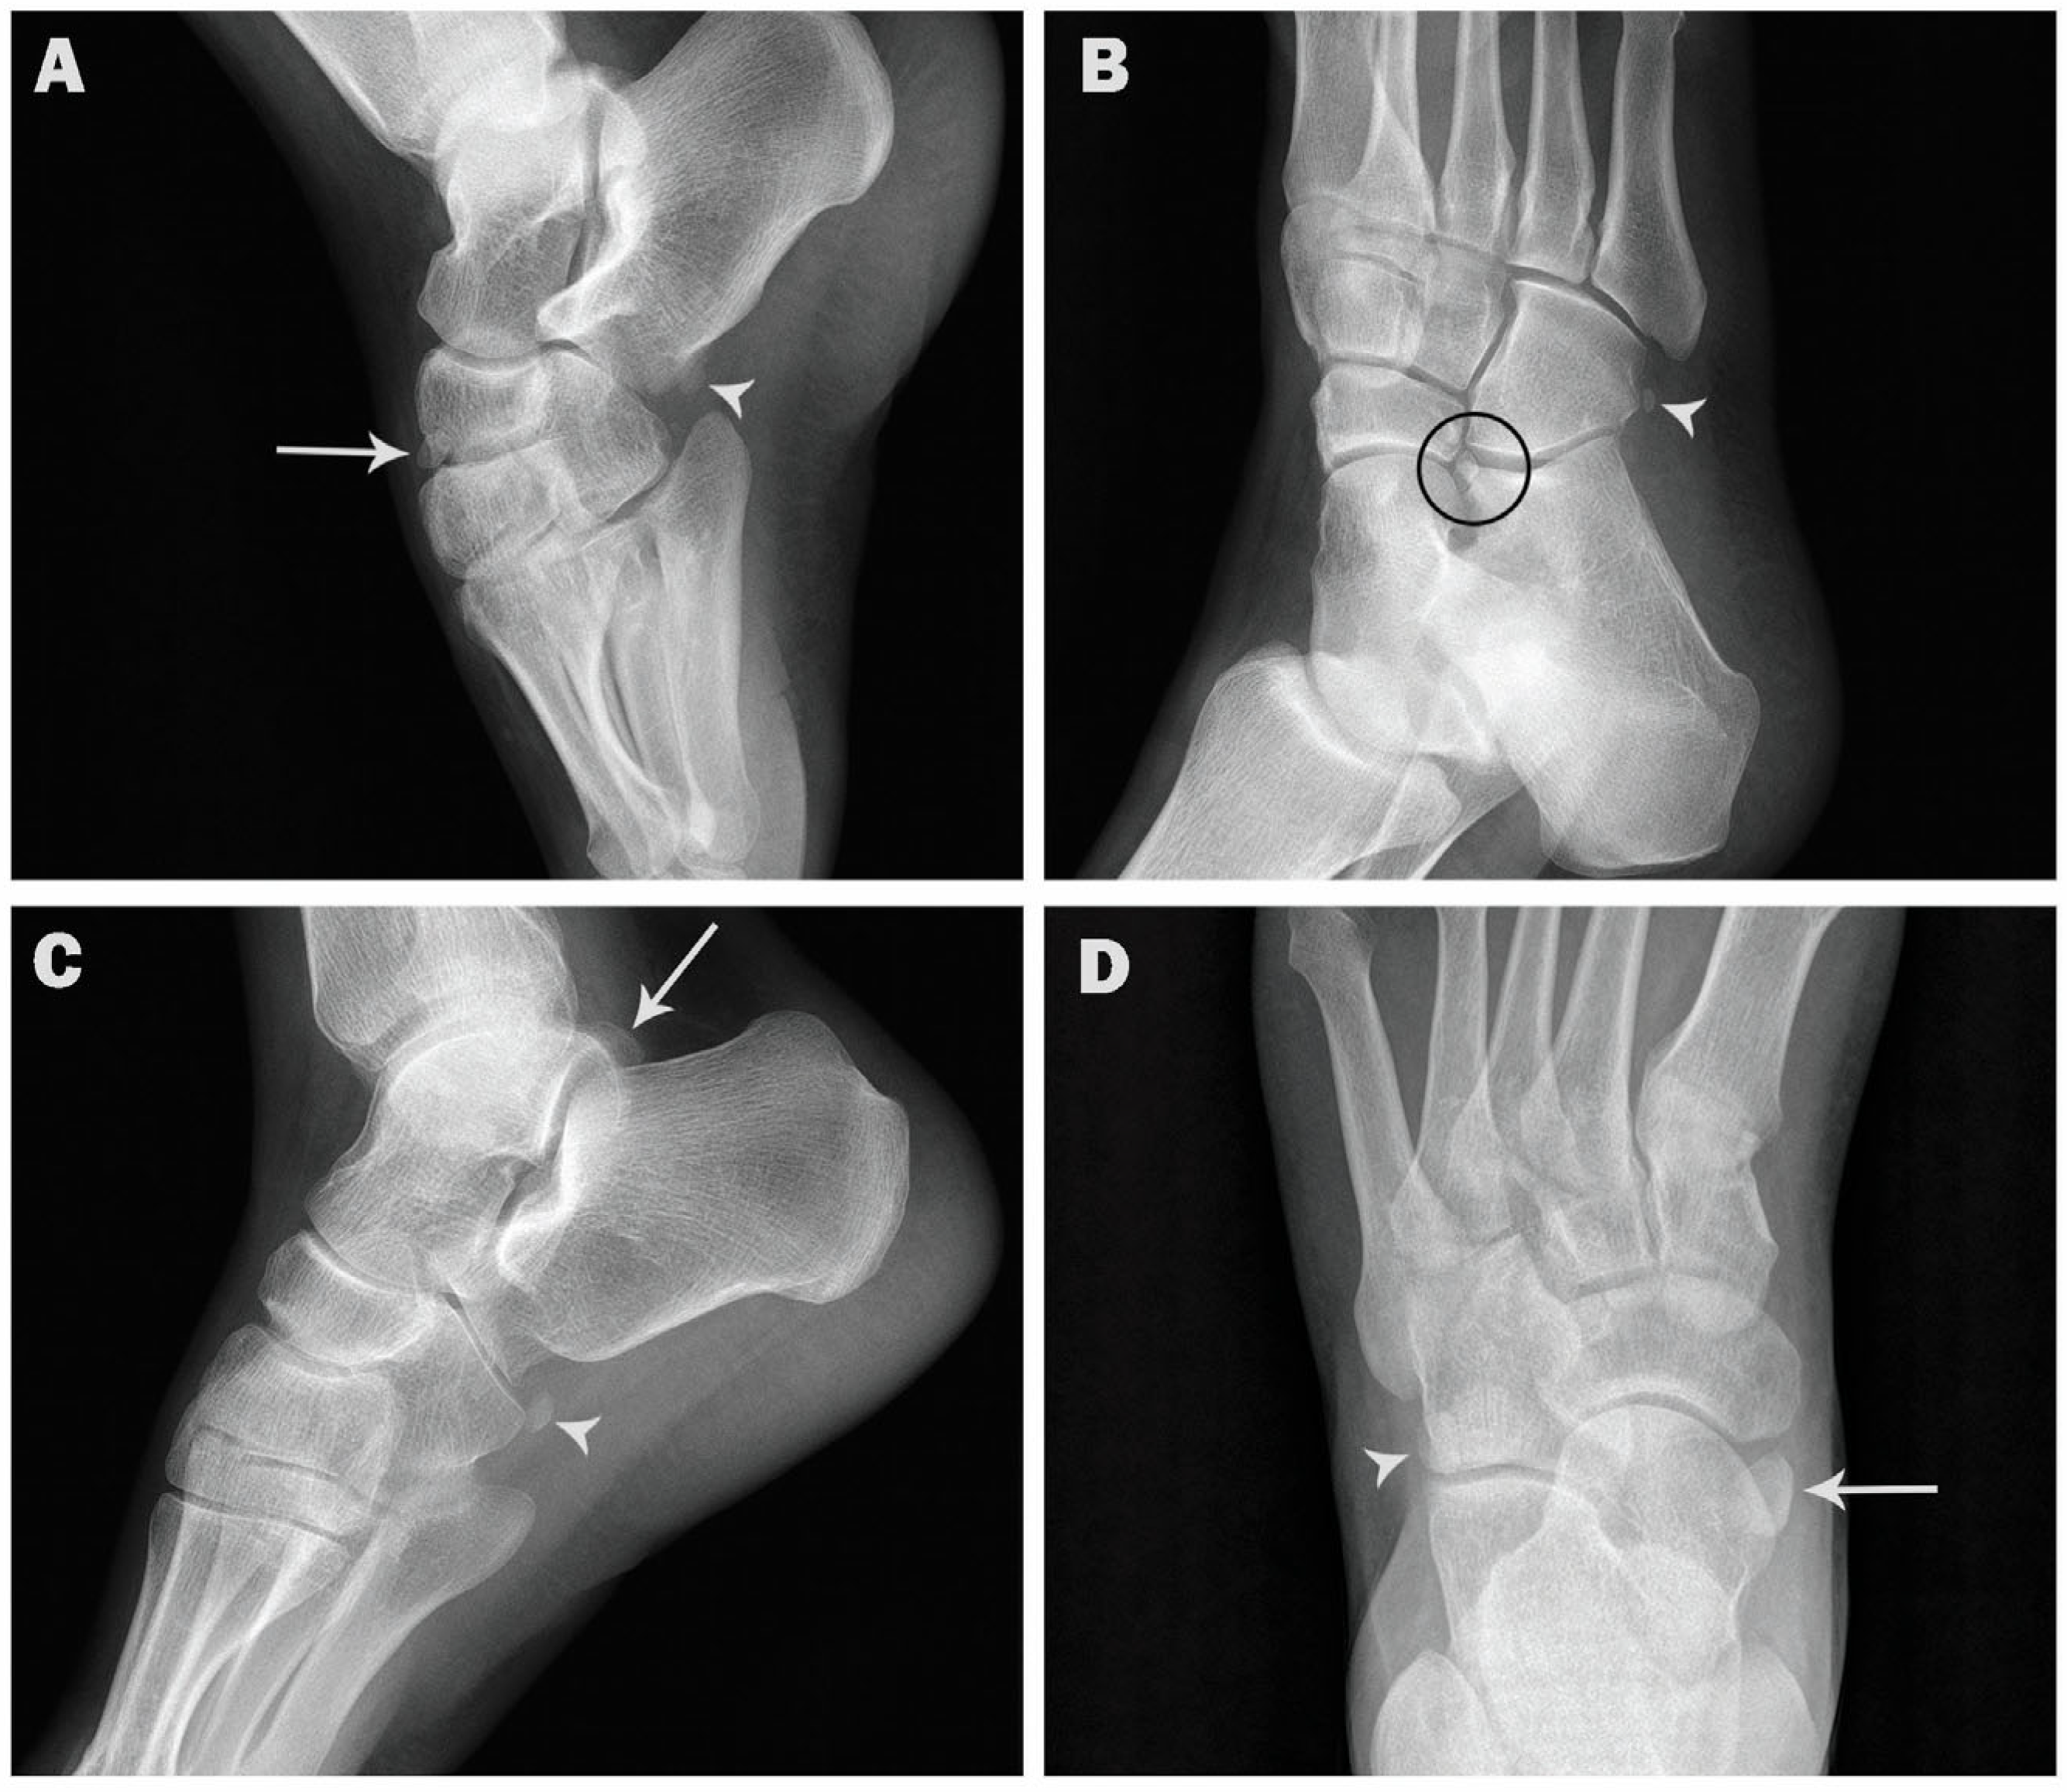

| Os trigonum | 154 (15.4) | 65 (13.0) | 89 (17.8) | 105 (15.6) | 49 (15.0) |

| Accessory navicular | 137 (13.7) | 77 (15.4) | 60 (12.0) | 99 (14.7) | 38 (11.7) |

| Os peroneum | 115 (11.5) | 64 (12.8) | 51 (10.2) | 81 (12.0) | 34 (10.4) |

| Os vesalianum | 11 (1.1) | 7 (1.4) | 4 (0.8) | 9 (1.3) | 2 (0.6) |

| Os calcaneus secundarius | 3 (0.3) | 2 (0.4) | 1 (0.2) | 2 (0.3) | 1 (0.3) |

| Os supratalare | 3 (0.3) | 2 (0.4) | 1 (0.2) | 1 (0.1) | 2 (0.6) |

| Os subfibulare | 6 (0.6) | 2 (0.4) | 4 (0.8) | 3 (0.4) | 3 (0.9) |

| Os supranaviculare | 7 (0.7) | 6 (1.2) | 1 (0.2) | 4 (0.6) | 3 (0.9) |

| Os infranaviculare | 3 (0.3) | 2 (0.4) | 1 (0.2) | 2 (0.3) | 1 (0.3) |

| Os subtibiale | 1 (0.1) | 1 (0.2) | 0 (0) | 0 (0) | 1 (0.3) |

| Os talotibiale | 4 (0.4) | 3 (0.6) | 1 (0.2) | 2 (0.3) | 2 (0.6) |